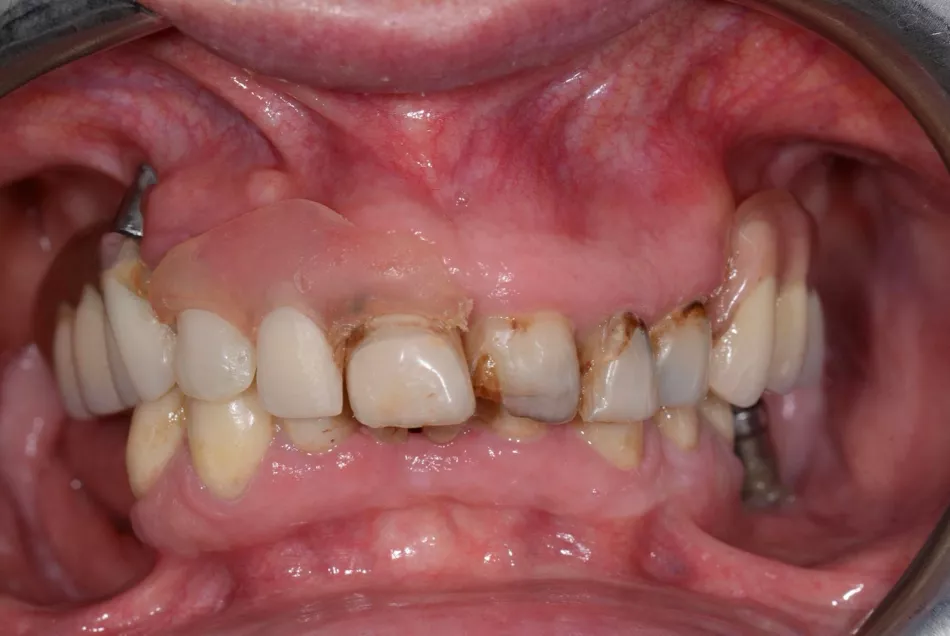

The patient was a 70-year-old woman who presented with the chief complaint of wanting to restore her ability to smile and chew comfortably. Her main expectation focused on improving esthetics, as she had expressed dissatisfaction with her dental appearance and wished to regain a natural, confident smile. She reported no systemic risk factors, was classified as ASA I, and was a non-smoker (Figs. 1,2).

Her dental history included multiple extractions, misplaced implants, and dental decay. Clinically, she demonstrated good plaque control and minimal soft tissue inflammation, although several remaining roots were present in both the upper and lower jaws. In the maxilla, the patient presented with an implant-supported removable prosthesis, and in the mandible, a fixed bridge, both of which were in poor condition (Fig. 3).

Fig. 3

After removing the upper jaw prostheses and the lower jaw bridge, the remaining teeth were found to be compromised. Some malpositioned implants were displayed in both arches (Figs. 4-8).